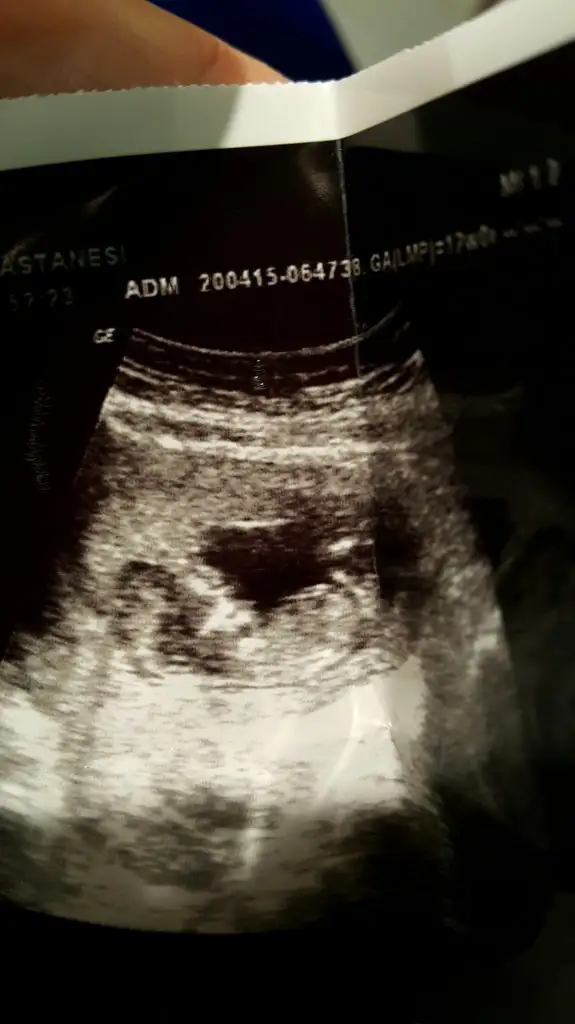

taze taze size tam 12 haftalik resim.yorumlarinizi alalim teyzeleri?

Arkadaslar benim bebegimi de yorumlar misiniz? Dr henuz cinsiyey icin cok erken oldugunu soyledi ama ben cok merak efiyorum.

ilk bebis mi benim iki oglan var. bu bebis de keseye gore ve kesedeki konuma gore erkek. Çin e göre erkek rusa gore kiz. nubu merak ediyorum:)